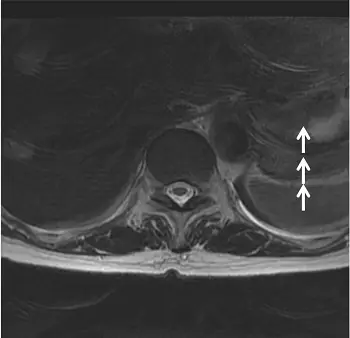

- 影像為上腹部/下胸腔的軸切面(axial plane)磁振造影影像。

- 圖中白色箭號指著在垂直方向(前後向,anterior-posterior)上出現的一系列重複、半透明的解剖構造輪廓(如皮下脂肪層或高訊號血管的殘影)。

- 這些殘影呈現週期性的排列,並橫跨了整個視野(FOV),覆蓋在正常的解剖構造之上。

- 這種沿著特定軸向(通常是相位編碼方向,phase-encoding direction)傳遞的重複性殘影,是典型的「鬼影假影(ghosting artifact)」,主要由掃描期間的週期性運動所引起。